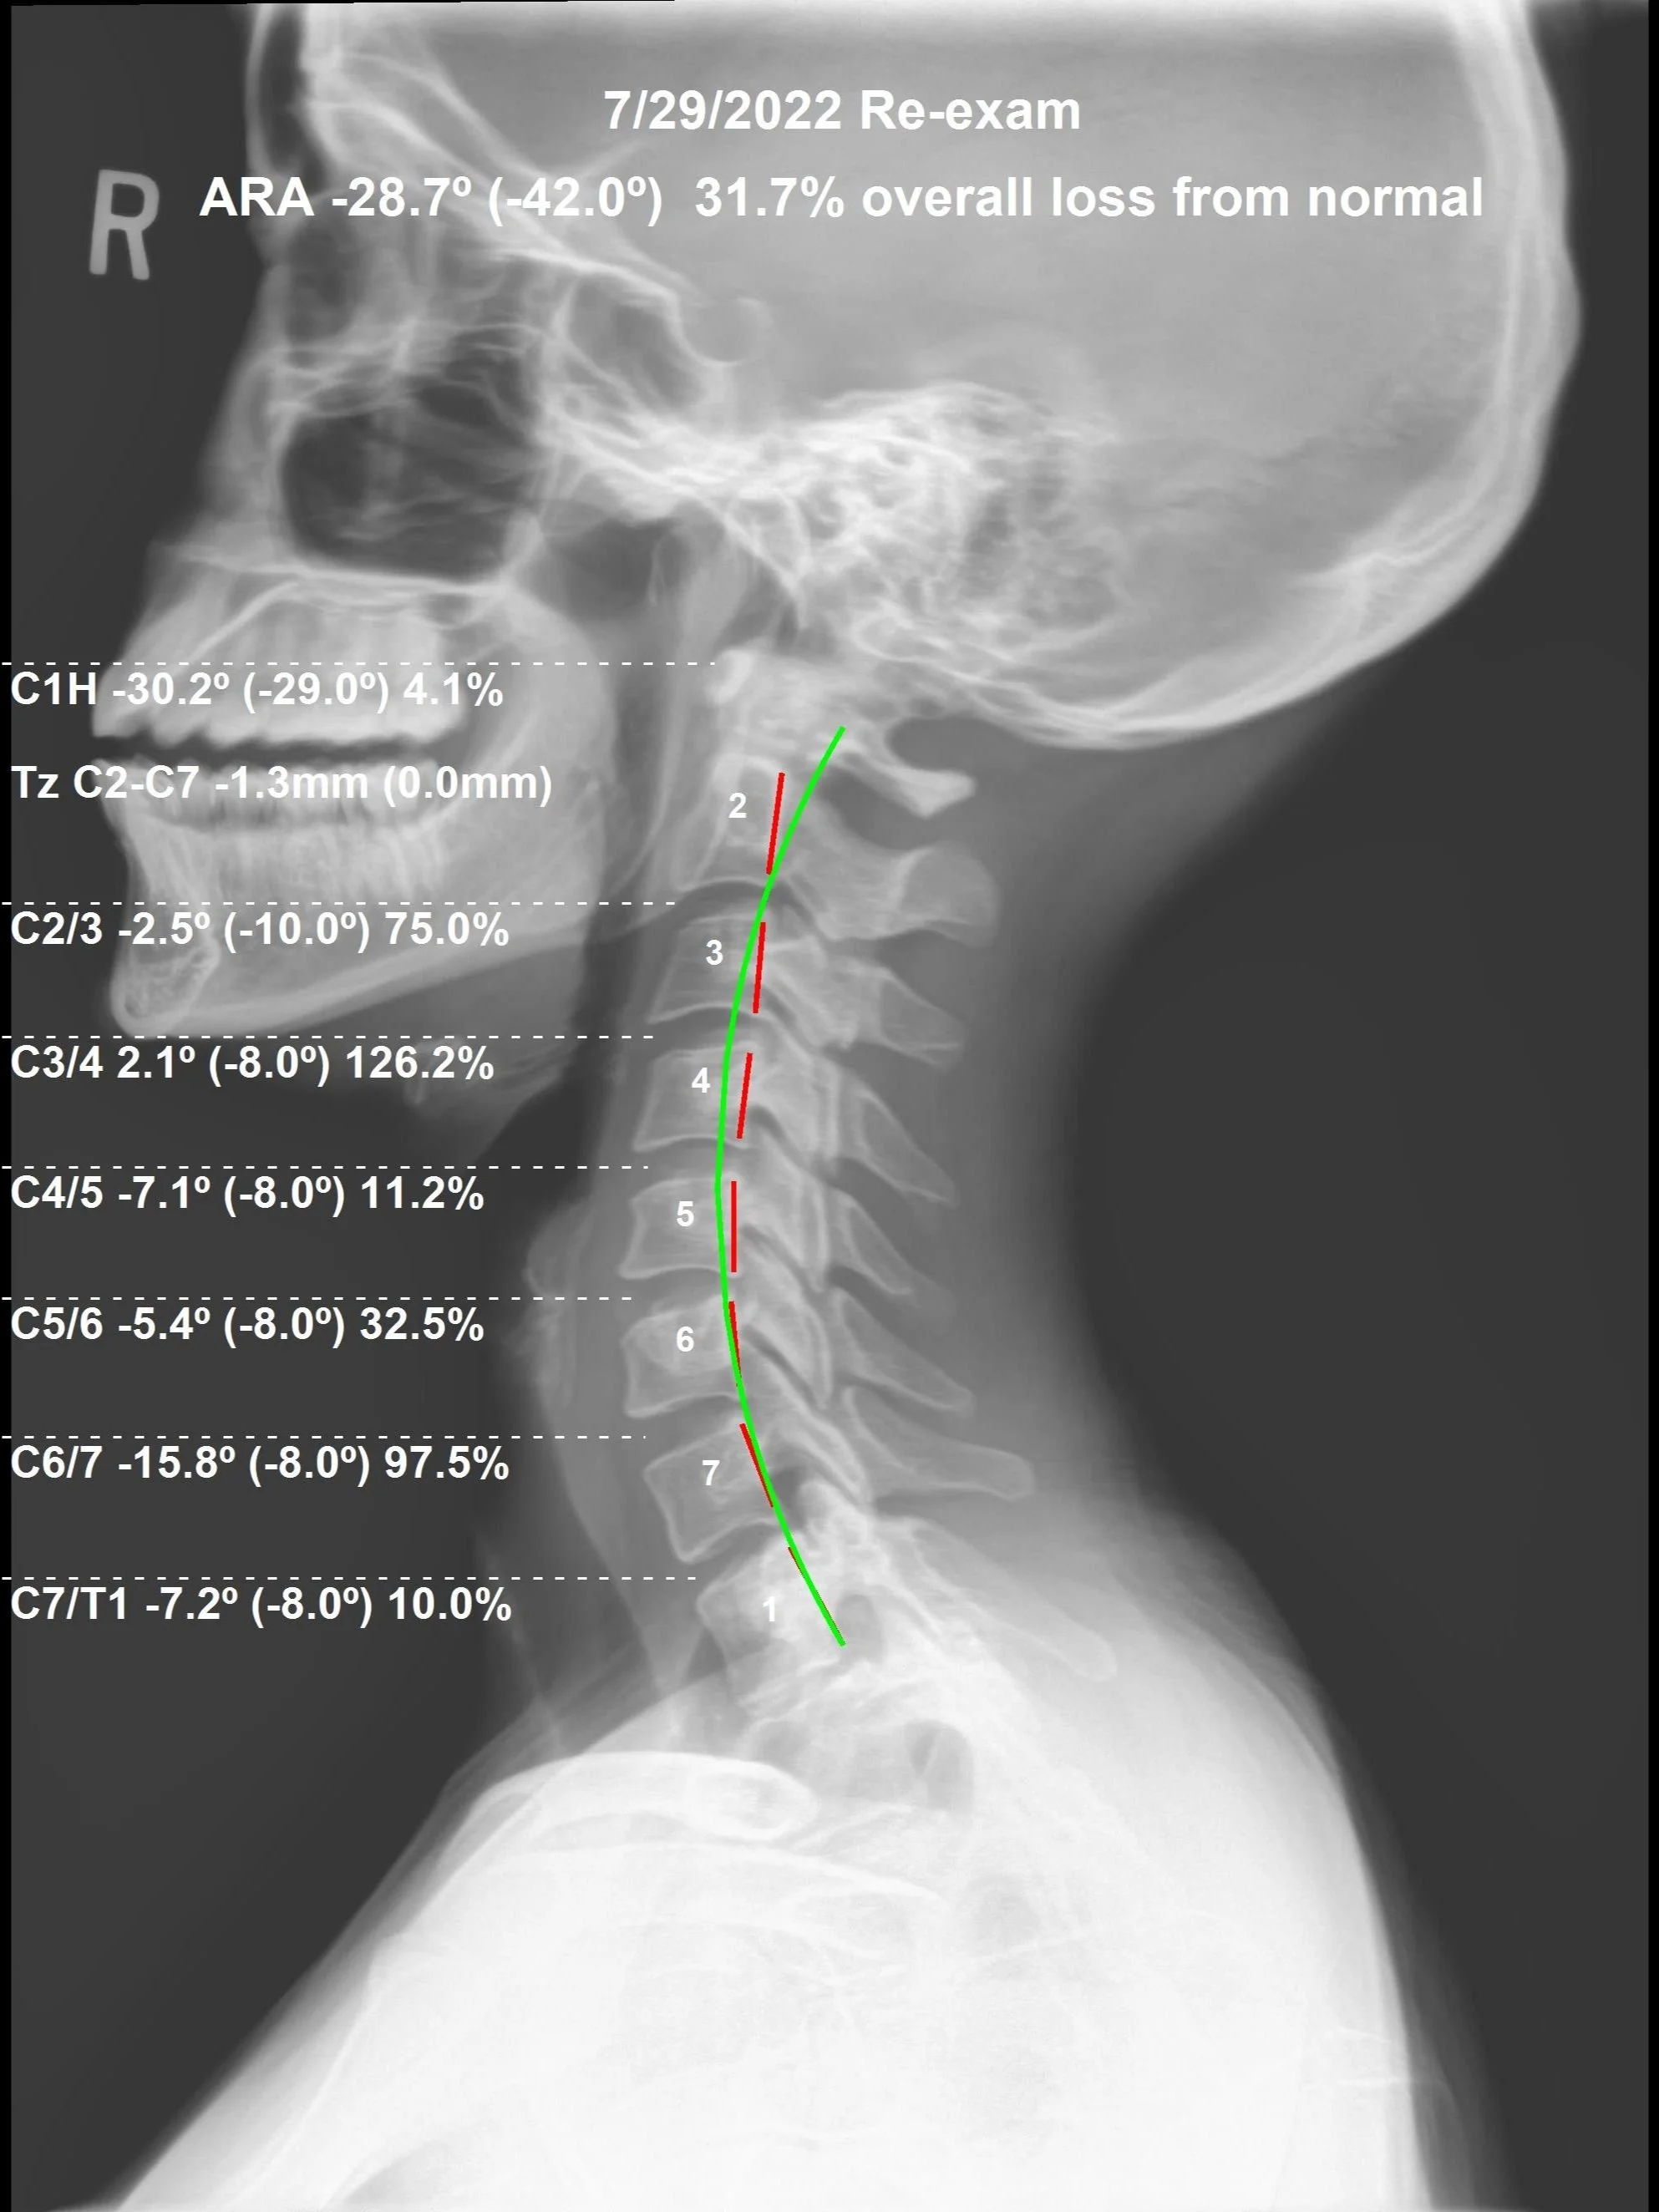

Correction of the Month